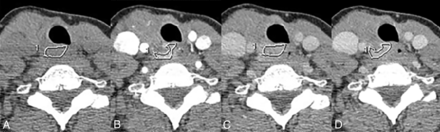

CT images were transferred to an ADW-2 workstation (GE Healthcare) with Volume Share 2, Version 4.4, software. A head and neck radiologist (J.M.D.) with >15 years of experience in head and neck radiology who was not blinded to the tissue type results drew ROIs around the recurrent lesions and areas of normal and diseased thyroid using freehand contouring. In the freehand contouring technique (Fig 1), the ROI was contoured to the visual outline of the lesion or the thyroid gland through the different phases of enhancement, with no requirement for the ROI size to remain constant. The outline from the largest area of enhancement representing the entire lesion was copied onto a similar site on the precontrast phase image. An attempt was made to place the contour 1 mm from the edge of the lesion to minimize the effects of partial volume averaging. Any visible surgical clips or calcifications associated with the lesions were excluded.

Freehand contouring method of drawing the ROI. In the freehand contouring method, the borders of the lesion were traced on images in the arterial (B), venous (C), and delayed (D) phases of enhancement, with no requirement for the ROI size to remain constant. The largest area, the venous phase in this example, was then copied onto the (A) precontrast phase, where the lesion contrast with background was typically worse.